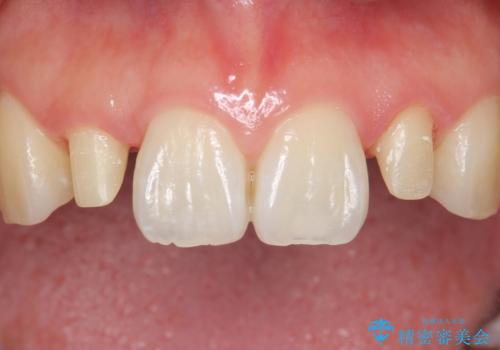

全顎的に歯並びにがたつきがあり、上の側切歯(上顎両側2)は生まれつき小さい歯(矮小歯)でした。

矯正治療後、矮小歯をセラミッククラウンにより理想的な歯の大きさに仕上げました。

- ¥280,000 (仮歯×2本、クラウン×2本)費用は治療当時の料金となります

クラウンの種類:オールセラミッククラウン スペシャル